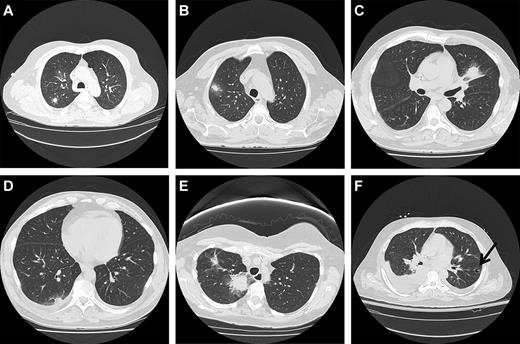

The HRCT scan is the best imaging technique to evaluate pulmonary infiltrates.27-29 A variety of studies in nonimmunocompromised patients have noted size, location, calcification pattern, change in size over time, edge characteristics, internal characteristics, number of nodules, attenuation, and contrast enhancement as features that provide important information.29 Lesions less than 1 cm are infrequently the result of neoplasm. Larger nodules are more likely to be malignant. Masses (lesions > 3 cm) are highly likely to be malignant. Malignant lesions are more likely to be in the upper lobes, whereas nonmalignant etiologies are more evenly distributed. Calcification is very suggestive of a benign granulomatous etiology if it has an organized diffuse, central, or laminar pattern. Lesions stable for more than 2 years are rarely malignant. Spiculated edges are suspicious for malignancy. Satellite nodules surrounding a central larger nodule are suggestive of granulomatous disease. An air-bronchogram within a nodule is suggestive of malignancy. Cavitation may be seen in both malignant and nonmalignant entities. Ground-glass opacification is suggestive of malignancy, such as adenocarcinoma in situ or minimally invasive adenocarcinoma of the lung. Figure 1 offers illustrative images of nodular lesions commonly observed.

Radiographs of different types of nodular lesions. (A) Solitary nodule. (B) Nodule with surrounding ground-glass halo. (C) Mass-like consolidation with surrounding halo of ground-glass opacity. (D) Peripheral pleural-based nodule with pleural effusion. (E) Large central irregular speculated density with surrounding ground-glass opacity and smaller more peripheral speculated lesion. (F) Cavitary nodule with sequestrum (air-crescent sign).